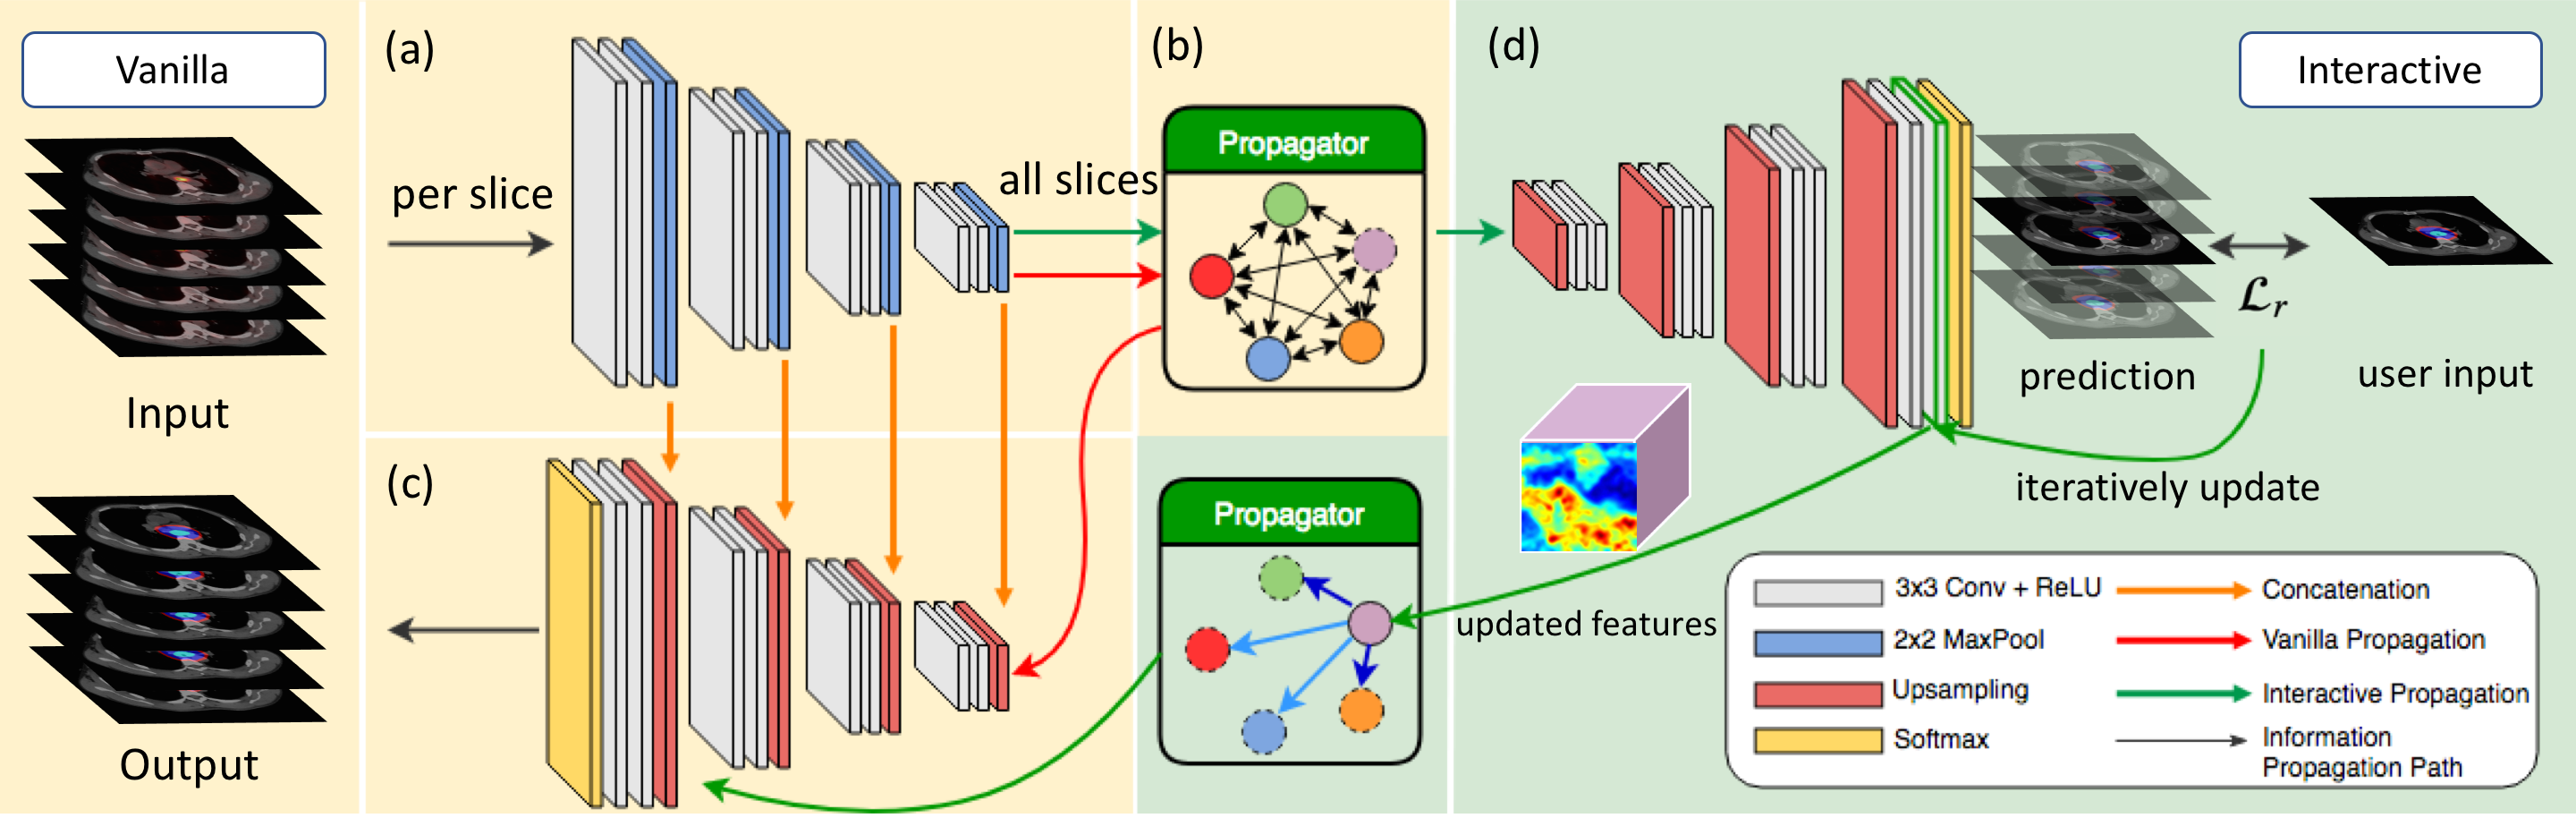

Fortunately, because of the adequate visual clue in tomography data, the delineation problem can be formulated for the convolutional neural network to solve. Instead of conventional 2D and 3D methods, we propose a novel convolutional gated graph network to tackle this task more efficiently. Specifically, given a sequence of PET-CT images, we first use an encoder to extract the deep representations of the images. Then we design a graph-based mechanism for our propagator to bridge the communication between these image slices and propagate the information among them. (Throughout this paper, we will use the term “image” and “slice” interchangeably.) Finally, a decoder will aggregate the high-resolution feature maps from the encoder and the slices propagated by propagator to predict the final segmentation map. The whole process is trained in an end-to-end manner.

For each sequence , our model first uses U-Net-like contraction part to obtain the feature maps of the images with various resolutions (see Figure 1 (a)). Then our Gated Graph Propagator (GGP, elaborated in the next paragraph) propagates spatial information throughout all slices in the sequence. (see Figure 1 (b)) Subsequently, the decoder combines deep representations of slices and high-resolution features from the skip connection of our encoder to perform up-sampling (see Figure 1 (c)). Finally, a pixel-wise softmax will output the final segmentation mask as our prediction. We use DICE loss to train our network.

Gated Graph Propagator.

We propose to use GGNN as the backbone of our GGP. Given produced from our encoder, we set up a learnable adjacency matrix , where is the set of indices for each slice in the sequence and is the set of indices for different types of edges. can be used to establish and weight the relationship between slices. For each pair of slice and , there will be a type of convolutional kernel to extract essential information from , weighted by :

| (1) |

| (2) |

Same as [6], we use Gated Recurrent Unit like mechanism to update : (3) (4) (5) (6)

Interactive Setting. Furthermore, we collect representations of a sequence of slices, , with one of the representations for slice was replaced with the user input representation to form the propagator for the interactive setting. We adopt the features from the last convolutional layer as the representations (see Figure 1 (d)). However, can’t be obtained directly, we approximate the representation for user input, , by iteratively updating the original features from the last convolutional layer until the prediction is close enough to the user input while inferencing :

| (7) |

where denotes the learning rate, is the user input, is the last convolutional layer and softmax and is the NLL loss. Once is obtained, we then train with a handcrafted adjacency matrix, where values of each entry are assigned according to its distance to slice . Then other slices in the sequence would be able to update its own representation regarding the information from the .